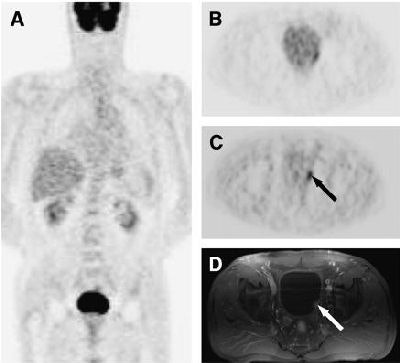

| (A and B) Transaxial (A) and sagittal (B) prediuretic F-18 FDG-PET images of 67-year-old woman previously treated for uterine adenocarcinoma show no convincing evidence of local disease recurrence. (C and D) Transaxial (C) and sagittal (D) postdiuretic F-18 FDG-PET images display sharply delineated focal hot spot (arrows) that corresponds to disease recurrence in vaginal stump, as confirmed by histologic analysis. Copyright © by the Society of Nuclear Medicine Inc. |

Seven foci persisted in this group, and the team found two that corresponded to recurrent cervical or endometrial carcinoma, which they suggested might have been missed if forced diuresis had not been applied.